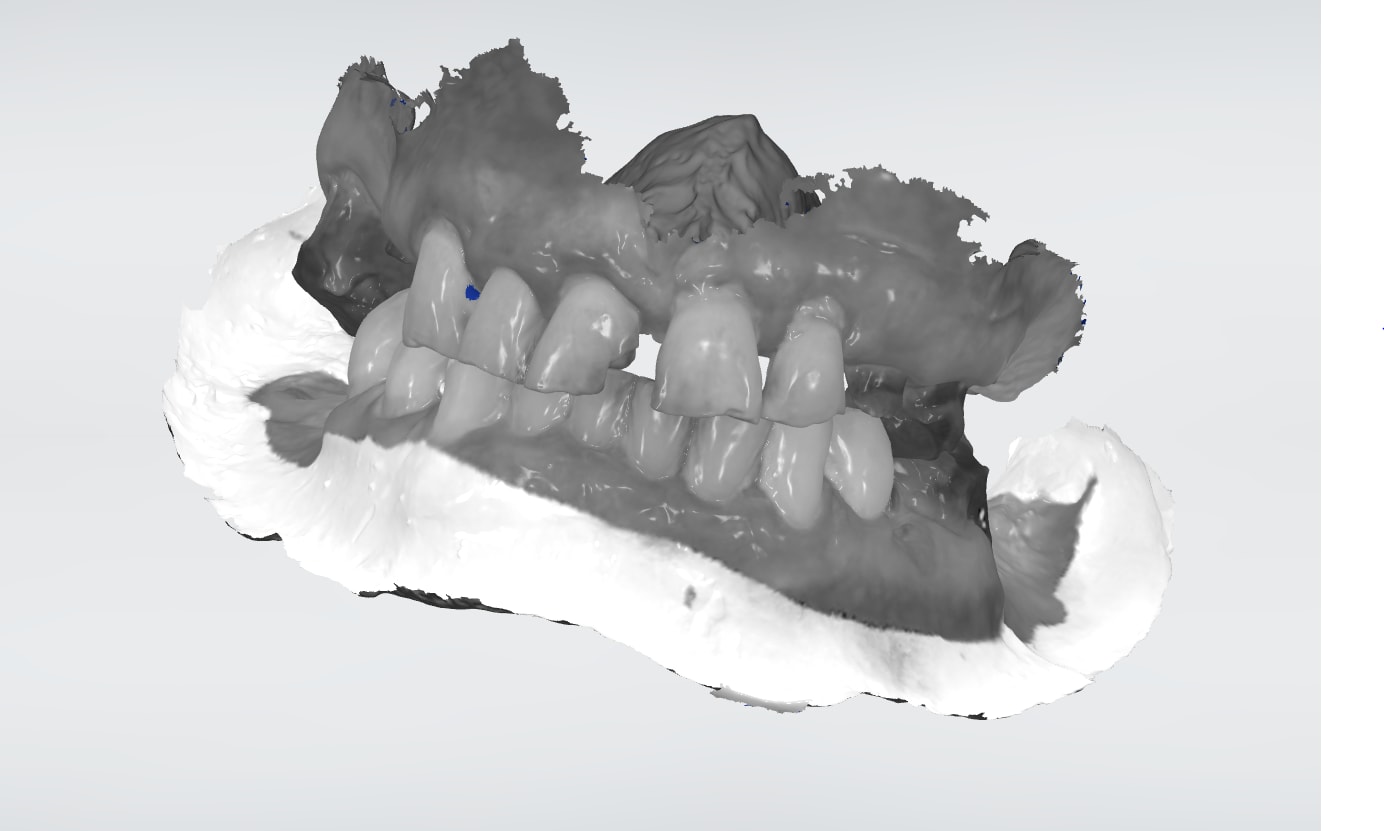

loi_cmu_précision_to4epq.png